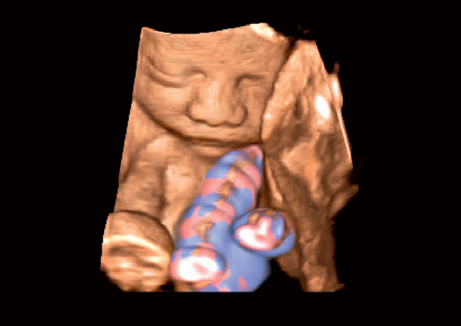

• 3D Color - цветное 3-х мерное изображение

• STIC Color - цветная объёмная визуализация сердца плода